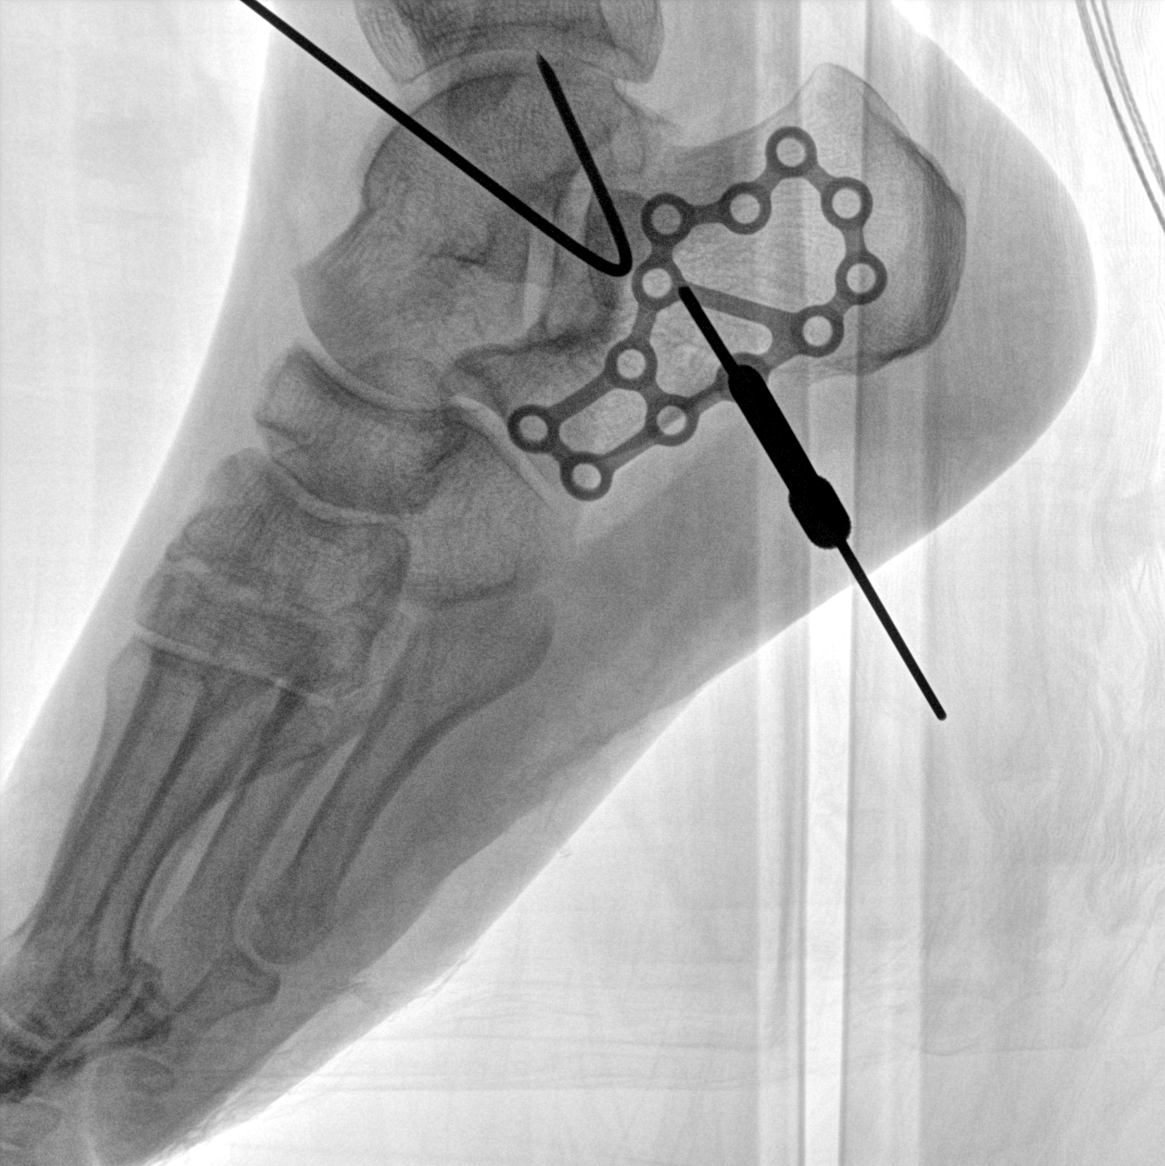

術(shù)中三維成像和橫斷面圖像提供多角度的手術(shù)診斷信息,輔助醫(yī)生進行術(shù)中評估判斷,諸如骨折復(fù)位情況和內(nèi)植入螺釘?shù)某叽绾臀恢?,輔助手術(shù)更好地完成。